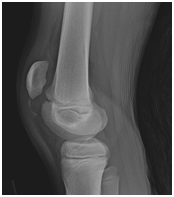

The patient, who suffered injuries during sport activities, is presented in this work. The patient has felt strong pain in the front part of joint after he had forced extensions from flexion knee position. After his arrival at Emergency service, x-ray photograph has been made (Figure 1). This x-ray shows sleeve type of fracture and during clinical examination certain preservation of extensor apparatus has been determined and at the same time conservatively treatment with immobilisation has been recommended. After four weeks immobilisation period, the patient, with protective bandage, is sent to physical therapy. In the following period physical therapist perceived slow rehabilitation of extension reinforcement as well as presence of swelling two months after the beginning of treatment. The patient continued to walk with dynamic ortho sis and returned to sport activities, although his rehabilitation was not completed. As a result, he felt cracking in the joint during the running. Considering the fact that he couldn’t get orthopaedic examination in a place where he is living, he didn’t see specialist for three months. In addition, he sees orthopaedic doctor with following difficulties; repeated fracture of distal fracture, high riding patella and full lack of function of extensor leg apparatus. New MRI and x-ray had been taken and it has been decided that reconstruction of extensor leg apparatus must be fixed by surgery.